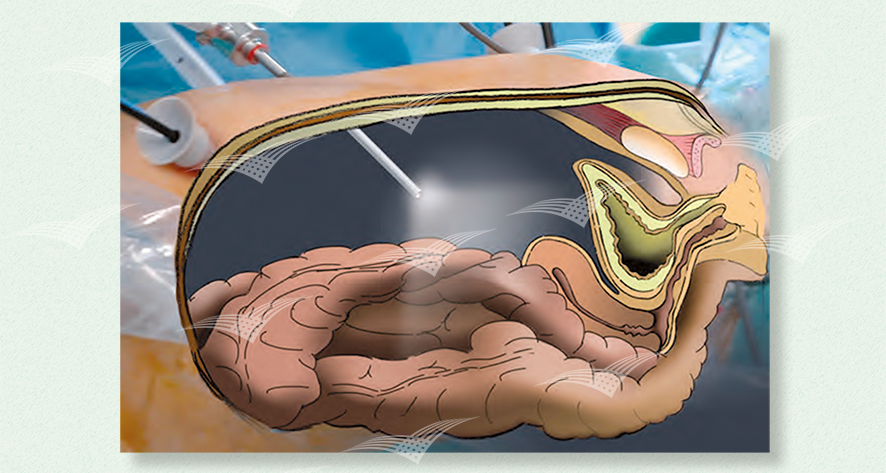

Laparoskopisches Gewebe Retraktionssystem T’Lift

T’Lift fixiert selbständig bis zu 1 kg und benötigt keinen eigenen Trokarzugang